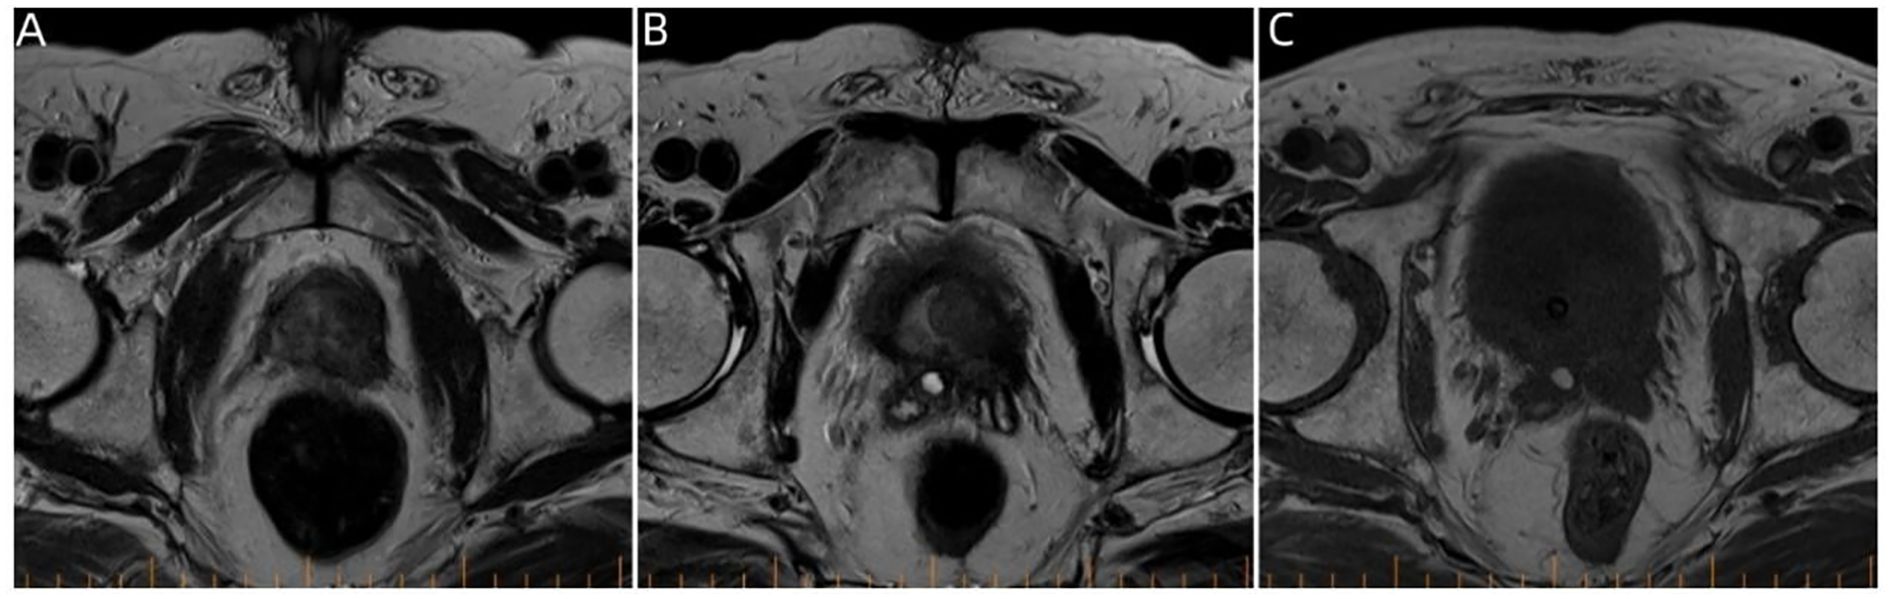

Figure 3

Three-panel MRI images labeled A, B, and C show axial cross-sections of a pelvic region. Each panel highlights variations in tissue density, with distinct dark and light areas representing different anatomical structures.

Figure 3. Pelvic magnetic resonance imaging. (A–C) Prostate magnetic resonance imaging findings on January 8, 2024, showing multiple round-like mass shadows within the prostate migratory zone thereof, with the central gland poorly demarcated from the peripheral zone.

A 74-year-old male patient presented with cough and sputum with intermittent blood in the sputum without obvious triggers. He was seen in a local hospital, where a computed tomography (CT) examination showed a right upper lobe lung mass, which was left untreated. He was seen in the Department of Thoracic Surgery of Xinhua Hospital, affiliated with Dalian University, on March 15, 2023, where he was treated with a biopsy of the cervical lymph nodes. The pathology showed metastatic adenocarcinoma (Figure 1A), and genetic testing found no mutations in EGFR, ALK, HER-2, ROS-1, RET, NTRK, BRAF, and MET. The following day, a chest CT was performed, which showed occupancy in the upper lobe (Figure 2A) and the middle lobe (Figure 2B) of the right lung. In addition, a 6.4-cm × 4.7-cm mass was seen in the apical segment of the upper lobe of the right lung, within which speckled calcification was observed, with an irregular margin and short burrs. The enhanced scan showed an uneven and obvious enhancement of the lesion, which was closely related to the adjacent pleura with an unclear demarcation (Figure 2A), and occupancy in the middle lobe of the right lung. Chemotherapy with pemetrexed + carboplatin + bevacizumab was administered for four cycles. A follow-up chest CT on June 6, 2023, showed a 3.1-cm × 2.4-cm mass in the right upper apical segment of the lung (which was significantly reduced compared with that observed on March 15, 2023) (Figure 2C), and the lesion in the middle lobe of the right lung was roughly similar to the previous one (Figure 2D). The patient’s symptoms such as coughing, coughing up sputum, and coughing up blood were significantly relieved after the treatment, and he stopped the treatment on his own. In September 2023, the patient was admitted to our hospital due to progressive urinary difficulty, and the pathology was suggested: prostate cancer (Figure 1B). He was given bicalutamide and leuprolide for endocrine therapy. On January 8, 2024, prostate magnetic resonance imaging showed that the prostate gland was slightly enlarged, approximately 4.3 cm × 3.8 cm × 2.6 cm, and the prostate peritoneum was poorly illuminated. The prostate migratory zone showed multiple rounded masses, with the larger ones measuring approximately 1.8cm × 1.4 cm, presenting a low signal on T1-weighted imaging (T1WI) and a slightly high signal on T2-weighted imaging (T2WI), with a poorly demarcated central gland and peripheral zone. The peripheral zone was not clearly demarcated. The central gland and the peripheral band were not clearly demarcated. The peripheral band showed a mass shadow of approximately 1.6 cm in length at 5 o’clock, which broke through the peritoneum and had a slightly restricted diffusion. The border was not clear (Figures 3A–C). Pathology consultation of the prostate specimen was given, which was consistent with a diagnosis of PCa, supplemented with immunohistochemistry of the cervical lymph nodes, prostate-specific antigen (PSA) (part 3+) (Figure 1C), P504S (3+) (Figure 1D), TTF1 (−), CK7 (−), CK20 (−), napsin A (−), and P40 (−), consistent with metastatic carcinoma of the prostate. The patient was recommended to further undergo bronchoscopy or percutaneous lung puncture biopsy in order to clarify the pathologic diagnosis and treat the lung cancer according to the pathologic diagnosis. However, the patient had peripheral lung cancer, and the lung puncture biopsy had a high risk of pneumothorax due to the long puncture path. Moreover, the tumor tissue could not be retrieved by bronchoscopy. Therefore, the patient’s family members refused to accept lung puncture biopsy and bronchoscopy and gave up the further genetic testing and molecular targeting therapy. They also refused to accept tumor resection of the right upper lobe of the lung and demanded that chemotherapy and immunotherapy be selected for the chemotherapy regimen for the lung cancer. Considering that patients with PCa can survive for a long time but those with lung cancer have a short survival period, and due to the patient having developed a weaker breath sound in the right lung compared with the left lung, we chose docetaxel, which is an effective chemotherapeutic drug for both PCa and lung cancer, combined with the immunotherapy drug karelizumab. The patient started two cycles of docetaxel + karelizumab on January 10, 2024. The review after treatment showed that the lung lesions were reduced and the prostate lesions, the neck lymph nodes, and other metastatic lesions in the lung were all stable. As the lesion in the upper lobe of the right lung was considered to have a high probability of being a primary cancer of the lung, the treatment was therefore effective. All other lesions were considered to be metastases of PCa. It is worth noting that, in the course of chemotherapy, new bone metastatic lesions appeared, and the possibility of the bone metastases originating from PCa was considered to be high. The disease progression of the patient is shown in Figure 4.